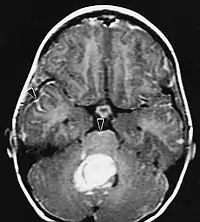

På-MRI viser en intrakraniel tumor som en massiv læsion, der kan blive mere selvlysende efter brug af kontrastmidlet. Der er dog altid en signalanomali i-Magnetisk resonansbilleddannelse, som indikerer tilstedeværelsen af neoplasi eller vasogent ødem. Sædvanligvis er øget luminescens (kontrastforbedring) tegn på en tumor af en højere grad af malignitet. En kontrastring er karakteristisk for glioblastom, hvor den selvlysende del svarer til den vitale del af den ondartede tumor, og den mørkere del-hypointense område svarende til vævsnekrose.

Patienter lider af en række karakteristiske symptomer på en fokal eller multifokal massiv læsion. MR viser sædvanligvis tumorer med homogen kontrastforøgelse i den dybe periventrikulære hvide substans. Multifokalitet og inhomogen forbedring er typisk for patienter med et svækket immunsystem. Analyse af CNS-lymfom er ekstremt vigtig i differentialdiagnosen af hjerneneoplasi. Det skal bemærkes, at administration af kortikosteroider kan føre til fuldstændig forsvinden af forstærkningen, hvilket gør diagnosen af læsionerne vanskelig. Hvis CNS-lymfom skal overvejes i differentialdiagnosen, bør kortikosteroider derfor undgås, medmindre masseeffekten forårsager et alvorligt og umiddelbart problem hos patienten.